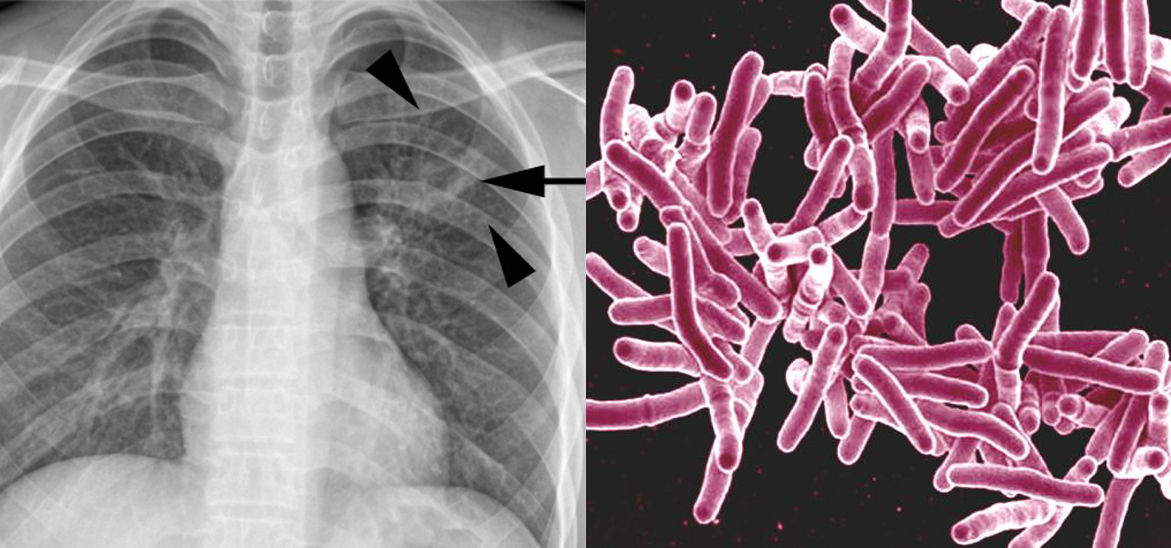

Archive: UCSF-led Commission Sets Out Targets to Eliminate Tuberculosis Within a Generation